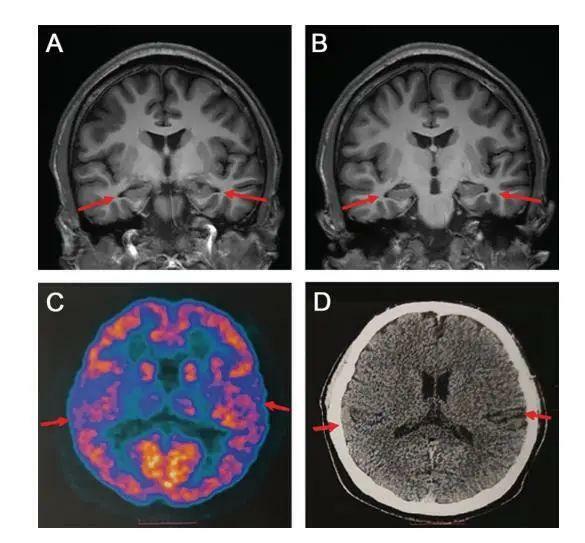

論文中表示,醫院為患者做了多種檢查,包括當前用於診斷阿爾茲海默病的最權威手段——腦脊液指標檢測和PET掃描,患者還接受了多種量表測試。掃描影像等顯示,患者存在輕度的腦萎縮等症狀,部分腦脊液指標也存在異常,最終患者被臨床診斷為阿爾茲海默症患者。

論文稱,該患者是目前已被報導的符合阿爾茲海默症診斷標準的最年輕病例。此外,該患者沒有家族遺傳病史,找不到其他引起記憶障礙的病因如遺傳、感染和系統性疾病。經過全基因組測序,未發現該患者攜帶任何風險或致病基因突變,排除了家族性AD的可能,其發病機制尚需進一步研究。